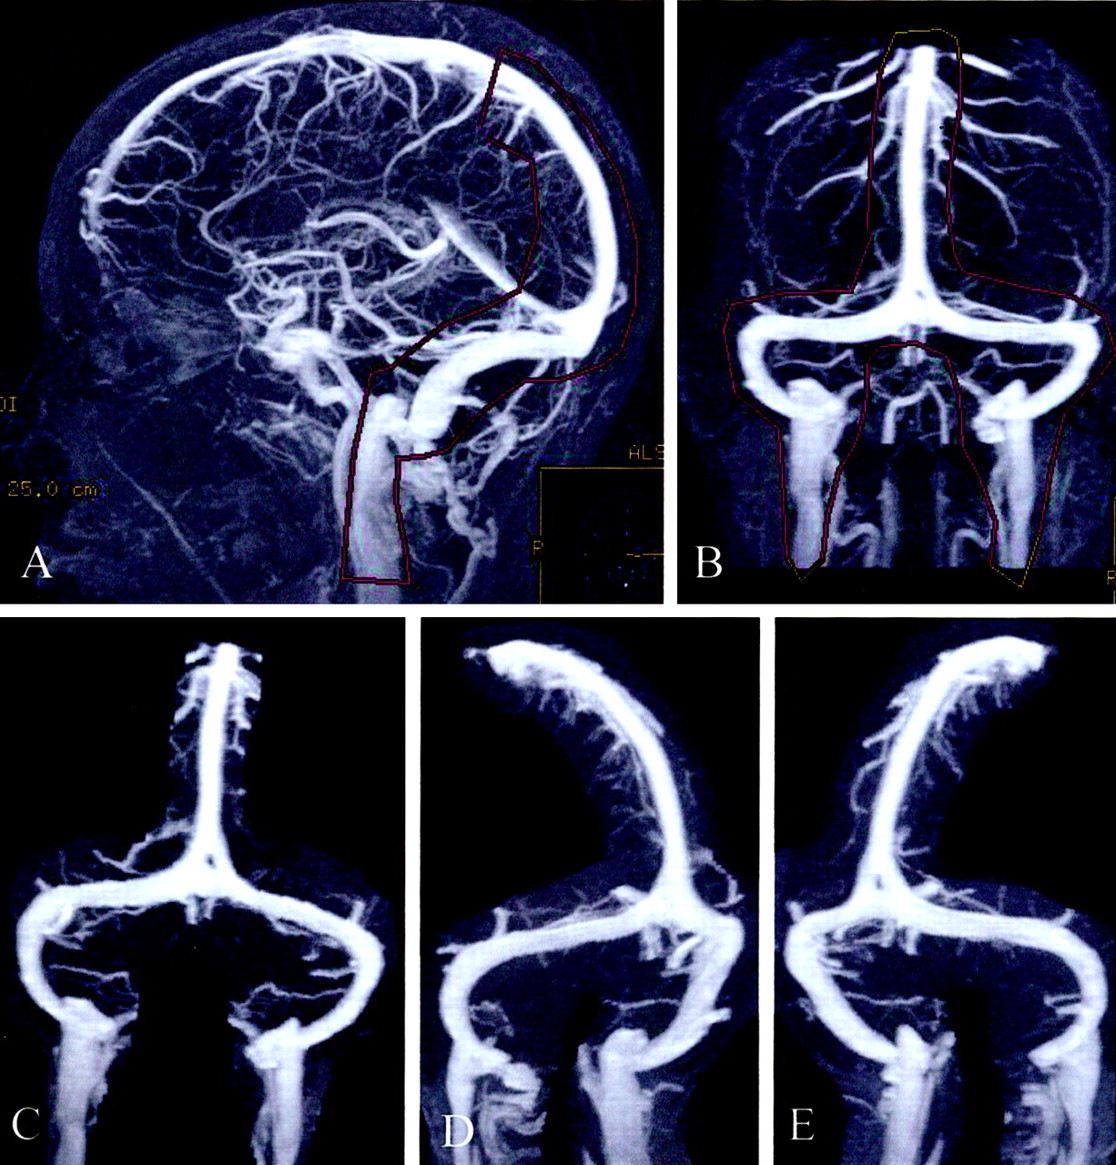

图1所示。Auto-triggered elliptic-centric-ordered控制病人的三维先生gadolinium-enhanced造影术。(一)横向和(B)前后的最大强度投影(MIPs)显示轮廓用来创建序列的分段MIPs获得每个控制和颅内高压症病人。(汉英)前后的左前斜(老挝),右前斜(RAO)分段MIPs。这三个选择拍摄的图像90张图片,电影圈的读者了。

29例颅内高压症履行必要的标准也经历了ATECO造影术先生在我们的机构(表)。这些患者的平均年龄为37.2岁,男女比例1:2.6。图3说明了发现ATECO MRV的典型颅内高压症患者。

共有88名患者被随机分配和评价这三个读者。两两之间的协议三个读者为他们蒙蔽分级CCS的每个病人(颅内高压症或控制)是使用加权kappa统计评估。7评价读者1和2之间的协议取得了kappa值为0.73;读者1和3之间kappa值为0.66;和读者之间的两个和三个kappa值为0.67。所有三个读者之间协议的总体水平是评估使用肯德尔和谐系数测量0.90表明优秀的协议在读者分级CCS。8-操作者特征(ROC)曲线(一个常用的工具来评估诊断测试的性能9)是构造为每个读者以及平均的三个读者。曲线下的面积及其相关标准误差是计算使用Mann-Whitney等价U测试(图4)。9每个ROC曲线下的面积从0.93到-0.97不等。ACCS控制的分布和颅内高压症病人如图(E) 1上首页网站(www.neurology.org首页)。敏感性和特异性ACCS使用一系列的计算值。ACCS值低于5.0最好的正常和异常的静脉导管之间的歧视。除了两个病人(假阴性),所有颅内高压症患者ACCS小于5.0。四个控制患者(假阳性)的ACCS小于5.0。小于5.0的ACCS原本正常的患者大脑的核磁共振显示颅内高压症的存在的敏感性93%,特异性93%。颅内高压症患者sinovenous狭窄的原因是由于一个明显的经管充盈缺损13个横向鼻窦45 vs extralumenal压缩。散点图和皮尔逊相关性之间的关系被用来评估CSF开启压力和ACCS (图5)。ACCS和脑脊液压力没有明显相关性。